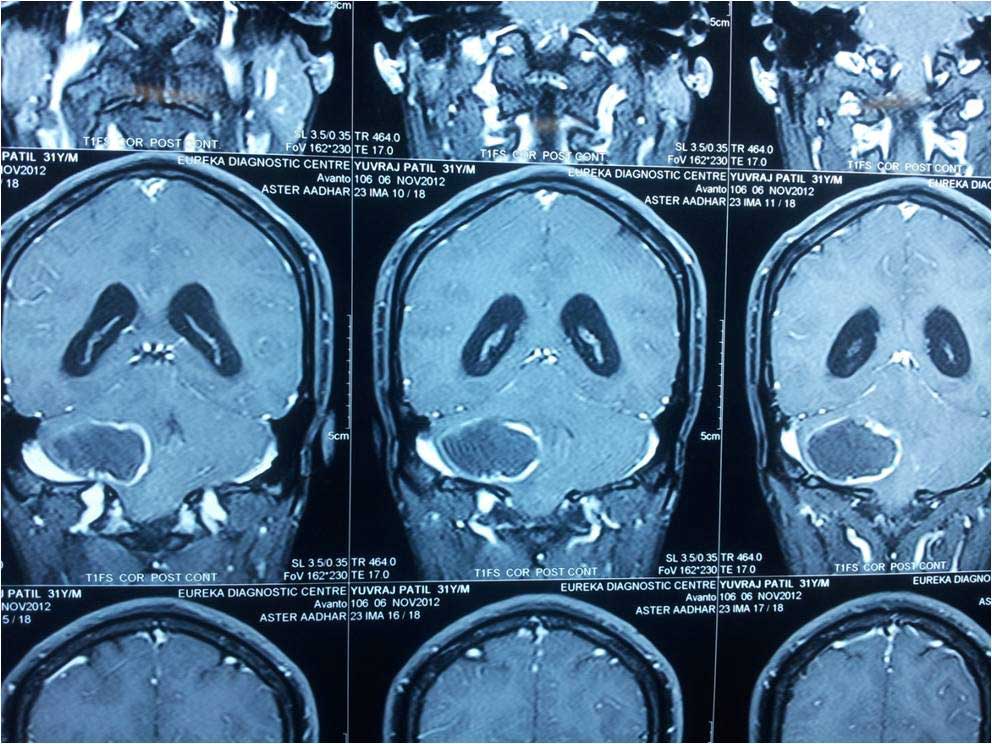

Brain Abscess Brain Abscess Post OP 2 Clinical Intra OP ,After Excising The Granuloma Intaop Scalp Abscess CT Scalp Abscess Cerebellar Abscess Post OP Clinical Cerebellar Abscess Brain TB Granuloma Post OP CT Scan Brain Infection Brain Abscess Preop MRI 2 Brain Abscess PRE OP Clinical 1 Brain Abscess PRE OP Brain Abscess Intraop 2 Brain Abscess Following Shunt Temporal Abscess T2W of TB Granuloma Scalp Abscess Preop CT Marking PRW OP MRI of TB Granuloma Post OP Clinical Photo Post OP Cerebellar Abscess Post OP Brain Abscess Intraop Specimen of Granuloma